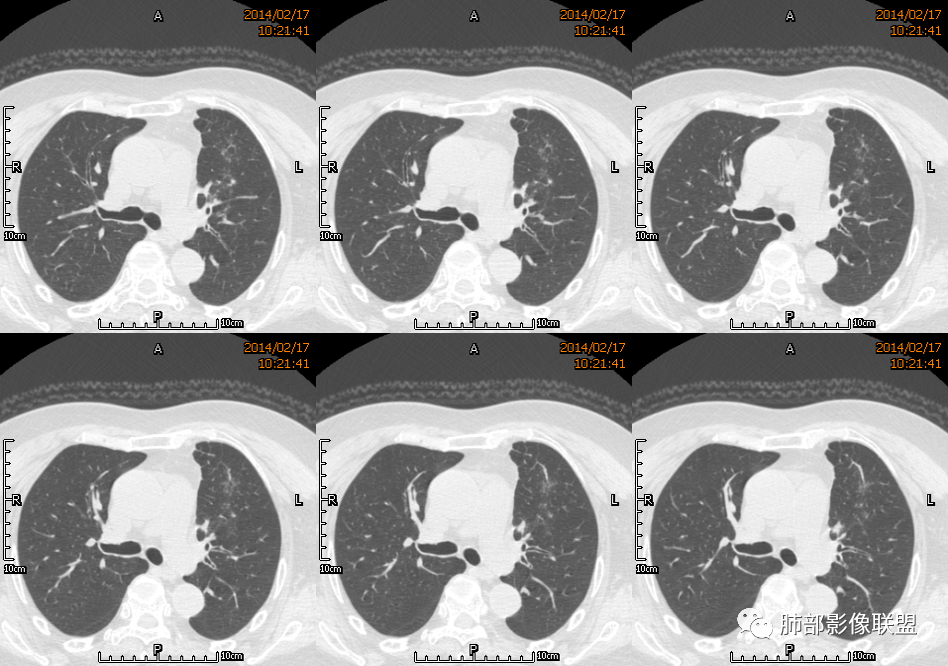

红星: 老年女性,咳嗽咳痰10天,痰中带血4天。左肺上叶前段胸膜下肿块影,沿支气管方向走行以膨胀生长为主,局部有收缩改变,支气管血管绝断,中间有小片状的坏死及小的空洞影,增强扫描病灶明显的强化,病灶周围网格状的小叶间隔增厚。拟左肺上叶前段浸润型腺癌并癌性淋巴管炎。鉴别诊断结核肉芽肿。

秦化君: 左肺上叶前段胸膜下软组织密度肿块影,边缘清晰,部分边缘膨隆,纵隔缘弧形内凹,脂肪界面清晰。肿块中心密度减低,支气管进入病灶后截断,似有扩张表现,病灶周围可见小叶间隔增厚,斑片影,近端支气管似管壁增厚。增强后明显强化,中心见低密度区。考虑:1.肉芽肿性炎?2.IMT?3.淋巴瘤?

傅昌瑜: 老年女性,咳嗽咳痰10天,痰中带血4天。左肺上叶前段胸膜下肿块影,沿支气管方向走行,膨胀生长为主,局部边缘似有收缩改变,中间有小片状的坏死,支气管进入,增强扫描病灶明显的强化,血管走形较自然(血管漂浮征?),病灶周围网格状的小叶间隔增厚。考虑淋巴瘤可能性大,注意鉴别炎性肉芽肿及肺腺癌。

水晶石头: 患者老年女性,咳嗽咳痰10天,痰中带血4天余。查血常规白细胞低;肿瘤标志物、凝血功能正常;血生化:蛋白低;C反应蛋白、血沉稍升高。胸部CT:左肺上叶前段胸膜下沿气管支气管走形肿块影,长轴与胸膜平行,见分叶、毛刺、支气管截断、空泡征象。增强明显强化,且见血管造影征及病灶内小灶低密度坏死区。左肺上叶尖后段见一结节灶。综合考虑恶性病变可能大,腺癌或淋巴瘤可能。鉴别诊断肺脓肿。

尘缘: 老年女性,咳嗽咳痰10天,痰中带血4天,白细胞及中性粒明显减低,轻度贫血。影像表现:左上叶肿块,边缘膨隆,局部平直,支气管稍扩张,进入后远端堵塞,内见小空洞及不规则坏死区,增强后强化明显,坏死边界较清,并见环状强化区,内部血管走行自然,周围见小叶间隔增厚呈大网格征。初步诊断:慢性炎性伴脓肿形成及肉芽组织增生。鉴别淋巴瘤及腺癌,先抗炎治疗后复查或直接穿刺明确。

宇宙星空: 外大内小,近端支气管壁增厚,爬树征,内部坏死不均匀,都比较典型了。支持结核,鉴别炎性肉芽肿、慢性脓肿。

王崇军: 老年女性,咳嗽咳痰10天,痰中带血4天。左肺上叶前段胸膜下 肿块影及段形态密度增高影,沿支气管方向走行,膨胀生长为主,局部有收缩改变,支气管进入并闭塞,中间有小片状的坏死及小的空洞影,空洞漂浮在坏死边缘,增强扫描病灶明显的强化,坏死边界清楚,似乎有轻度强化环,病灶周围网格状的小叶间隔增厚及小结节影,外侧胸膜呈糊墙改变。考虑为肺脓肿,这么大的病灶,竟然没有发烧,白细胞低,CPR轻度升高,均与脓肿不符,所以恶性待排,短期抗炎治疗后复查,病灶没有变化,脓肿就可以排除,恶性基本可以确定。

空格: 临床特点:老年女,血糖略高,低蛋白血症,白细胞低,提示有免疫下降的存在。机会性感染存在机会。黄浓痰一般常见于炎性病变,痰中带血则肿瘤多见,两厢pk,觉得黄脓痰胜,除非肿瘤继发感染一般不会黄脓痰。影像:一 、良性征像:1.病灶整体是个尖端指向肺门的三角形病灶;2.胸膜平直,胸膜外少量液体糊墙;3.支气管未见明显截断,内壁毛糙?4.近端支气管弥漫性增厚,结核脓痰咯出,看做引流支气管;5.多个层面病灶呈直边征,多角征,无明显分叶;6.病灶内坏死边缘光整,伴小气泡。小叶间隔增厚光滑锐利,无结节,不太像癌淋。二、恶性征像:部分层面向胸膜外突,略有占位效应。总体考虑感染性病灶,霉菌可能。结核抗体阴性,可以排除?

刘和林: 老年女性,咳嗽咳痰10天,痰中带血4天。左肺上叶前段胸膜下 肿块影,沿支气管方向走行,膨胀生长为主,局部边缘似有收缩改变,中间有小片状的坏死,坏死区内见小气泡,支气管进入、部分填充、部分末端稍显扩张,增强扫描病灶明显的强化,周围肺不干净,其上肺见小叶间隔增厚。肺癌、淋巴瘤、炎性肉芽肿?肺癌:支气管末端稍扩张,周围类似树芽征改变,不太符合。淋巴瘤:数个小气泡,明显强化,周围树芽征样改变,不太符合。

2.左肺上叶前段胸膜下块状影,不规则呈“逗点样”延向肺门区,边界清楚,未见分叶、毛刺及张力,表面不规则棘突,状如“火焰”或“日冕”。相邻胸膜增厚,未见栽赃、卫星病灶。

3.病灶密度不均,中央坏死液化并见气泡影,支气管及血管贴边进入,较均匀环形强化(显示多层结构),未见明确壁结节。